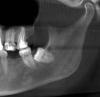

Сегодня было больно. Приступили к лечению нижней челюсти. Ценник на нижнюю челюсть - 200 тыс. Поставили 2 миниимпланта. Брекеты только на 4 дальних зуба. Учитывая дистальный прикус, на жевательные зубы добавили пломбировочный материал. Слинт также до сих пор ношу. Уже 348 дней. Обрезали, теперь только на 9 нижних зубов.

О, у меня все 4 были проблемные и росли в соседние 😅 они ещё и все не прорезались. И глубоко были. Я первые два слева отдельно удаляла. А вот третий и четвёртый справа за один раз. Снизу врач тоже очень долго удалить не мог, в процессе делал снимок. Верхний не хотел потом удалять в тот же вечер, но я очень просила) а верхний стали когда удалять- сразу нос заложило, он в пазухе был 🙈